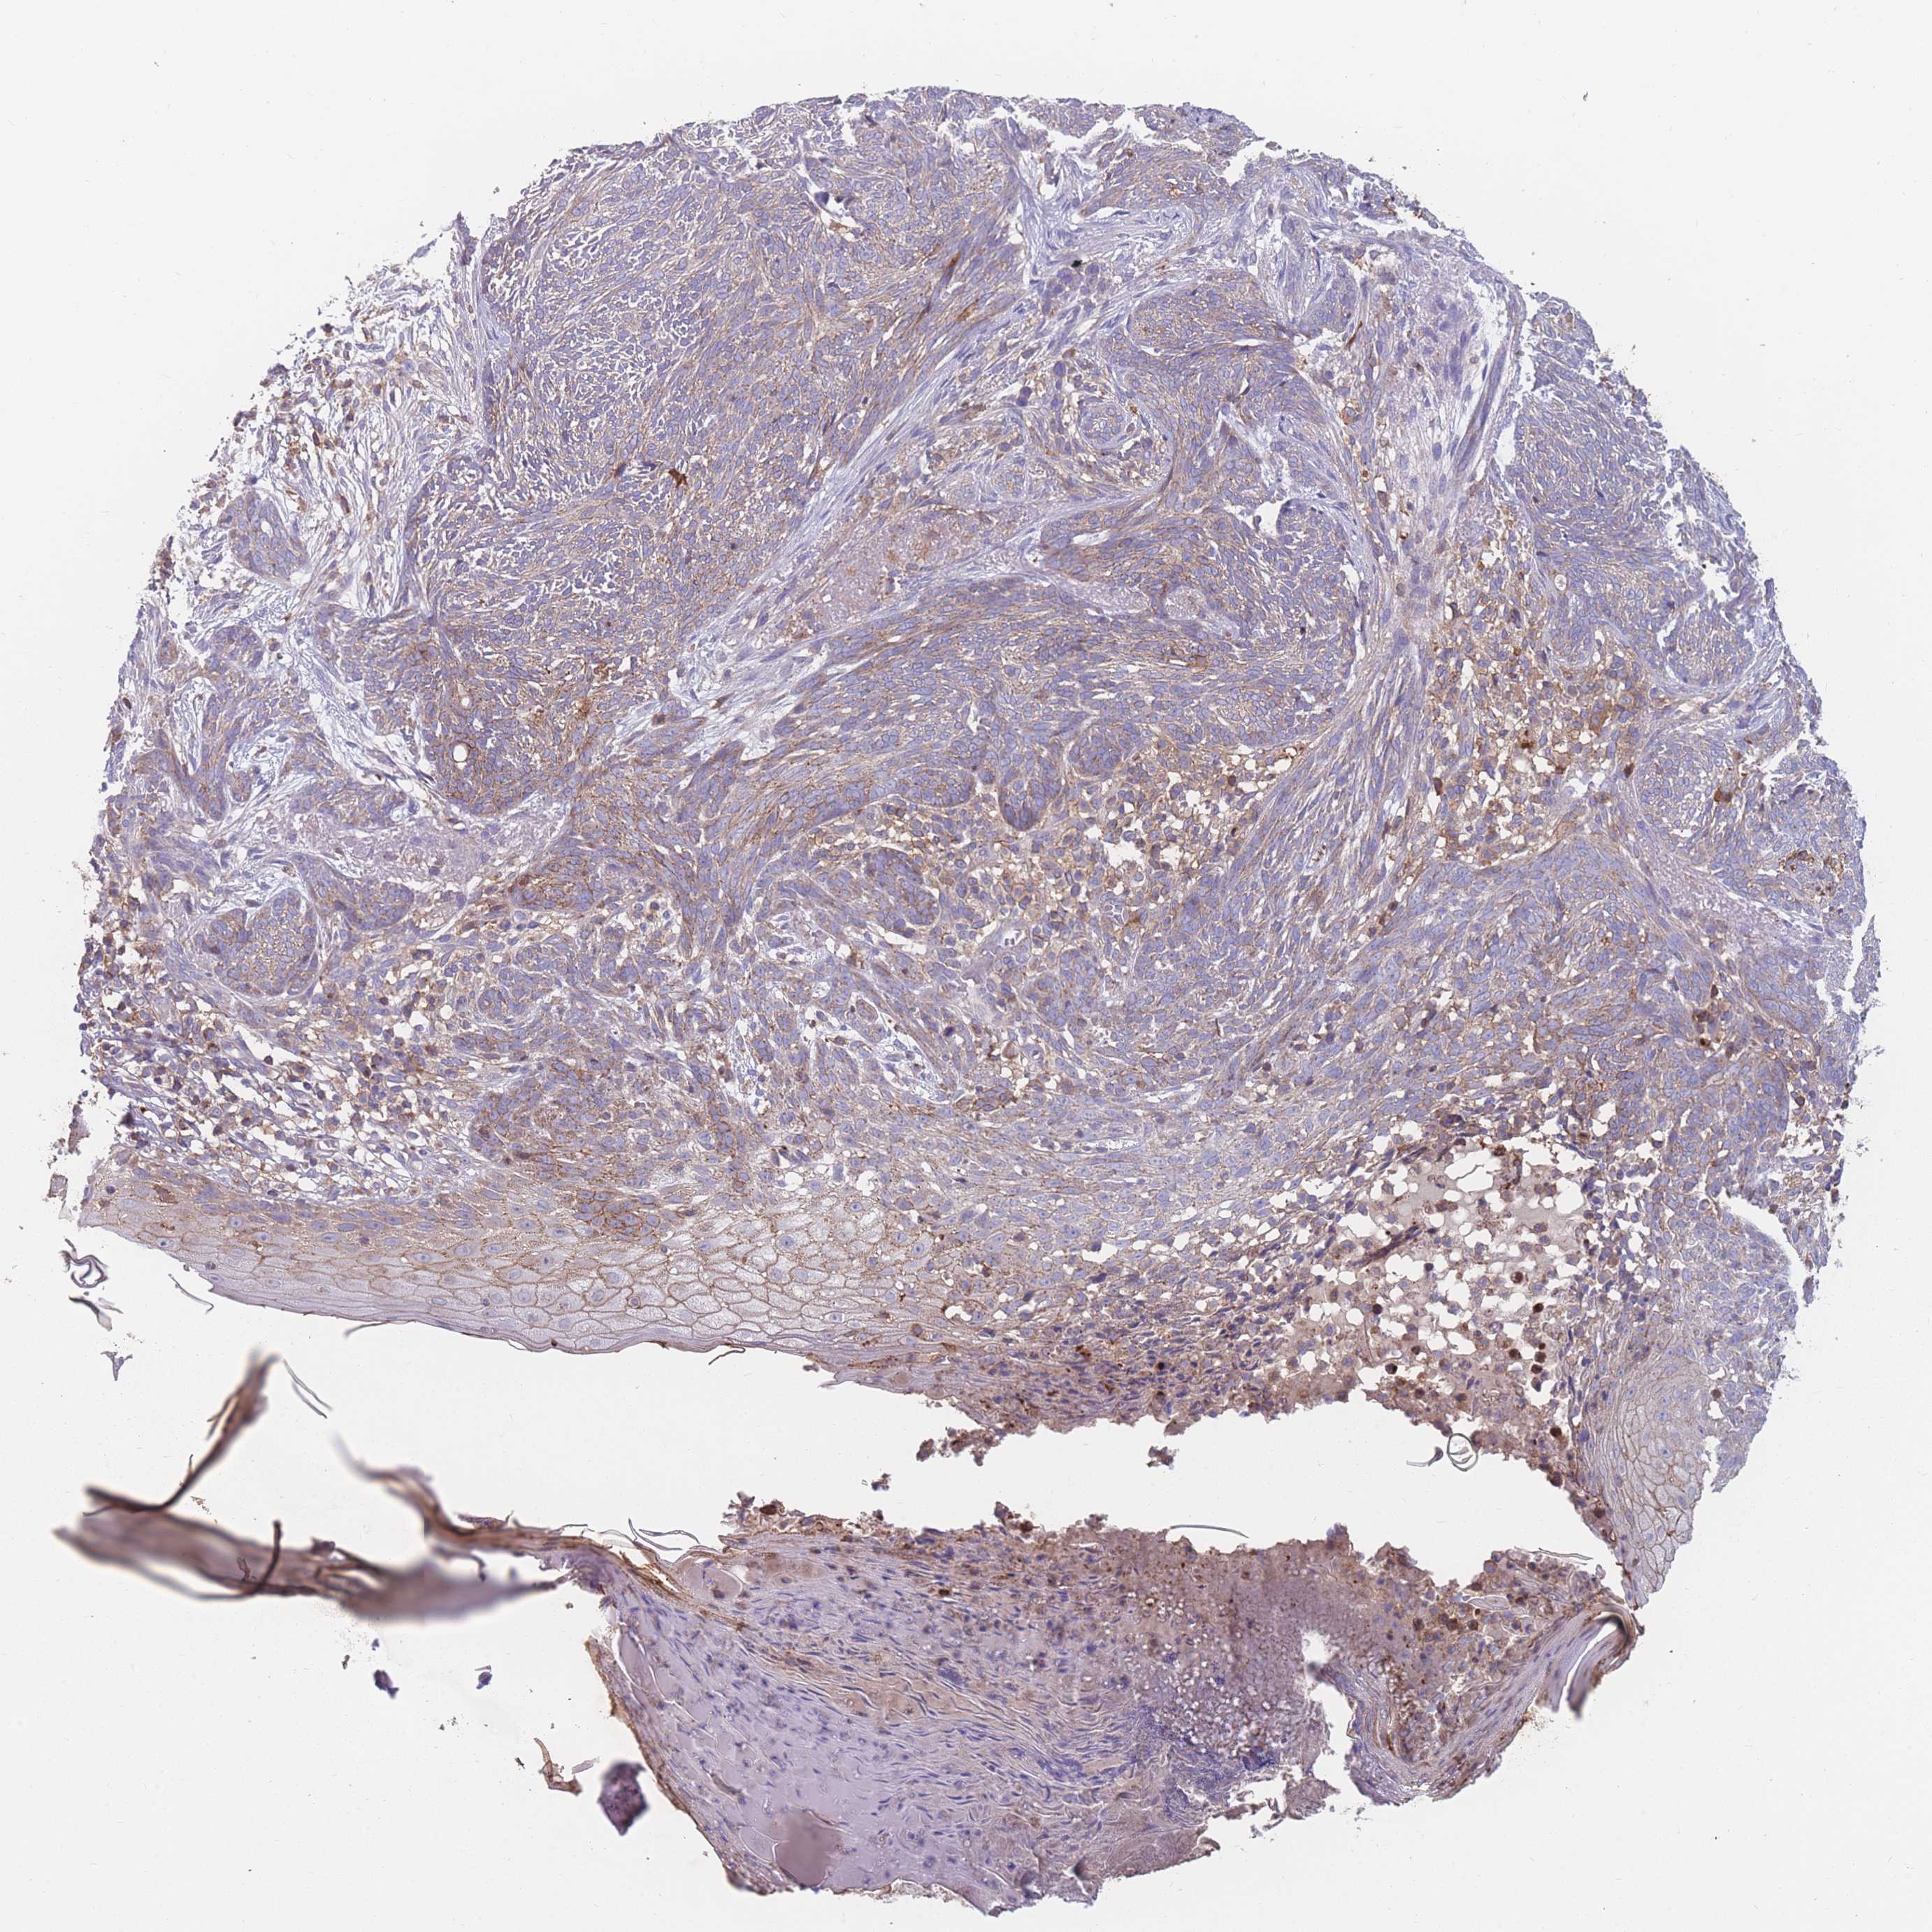

SKIN CANCER - Protein expressioni

A mouse-over function shows sample information and annotation data. Click on an image to view it in a full screen mode. Samples can be filtered based on level of antibody staining by selecting one or several of the following categories: high, medium, low and not detected. The assay and annotation is described here.

Each image is clickable and will lead to virtual microscopy that enables deeper exploration of all samples and also displays staining intensity scores, fraction scores and subcellular localization as well as patient and tissue information for each sample.

Antibody CAB080305

Squamous cell carcinoma, metastatic, NOS